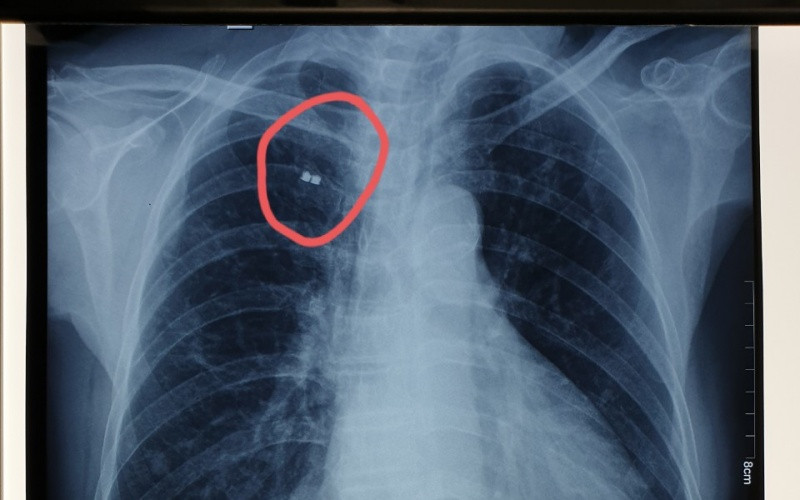

Vị trí mảnh bom trước khi gắp ra. (Ảnh: BVCC)

Khi ông N. đến khám bệnh tại Bệnh viện Xuyên Á Tây Ninh vì có một khối u sưng nề, gây đau ở vai phải; các bác sĩ đã chẩn đoán áp-xe vai phải và được tư vấn hướng điều trị là rạch tháo mủ ổ áp-xe. Bên cạnh đó, bác sĩ phát hiện có dị vật ở vùng ngực của ông qua phim chụp X-quang ngực thẳng nên đề nghị sẽ thực hiện đồng thời phẫu thuật lấy mảnh bom cho ông.

Dưới sự hỗ trợ của hệ thống C-Arm hiện đại (là hệ thống máy soi chụp X-quang và chiếu trực tiếp lên màn hình tăng sáng ngay tại phòng mổ), các bác sĩ Khoa Phẫu thuật Tim mạch - Lồng ngực xác định được chính xác vị trí mảnh bom. Ê-kíp phẫu thuật tiến hành gây tê tại vị trí mảnh bom, rạch da khoảng 2cm ở vị trí tê, bóc tách qua các lớp cơ thành ngực để tiếp cận mảnh bom nằm ở bờ dưới xương sườn số 2 trên đường trung đòn. Mảnh bom có kích thước khoảng 0,5cm đã được lấy ra dễ dàng.